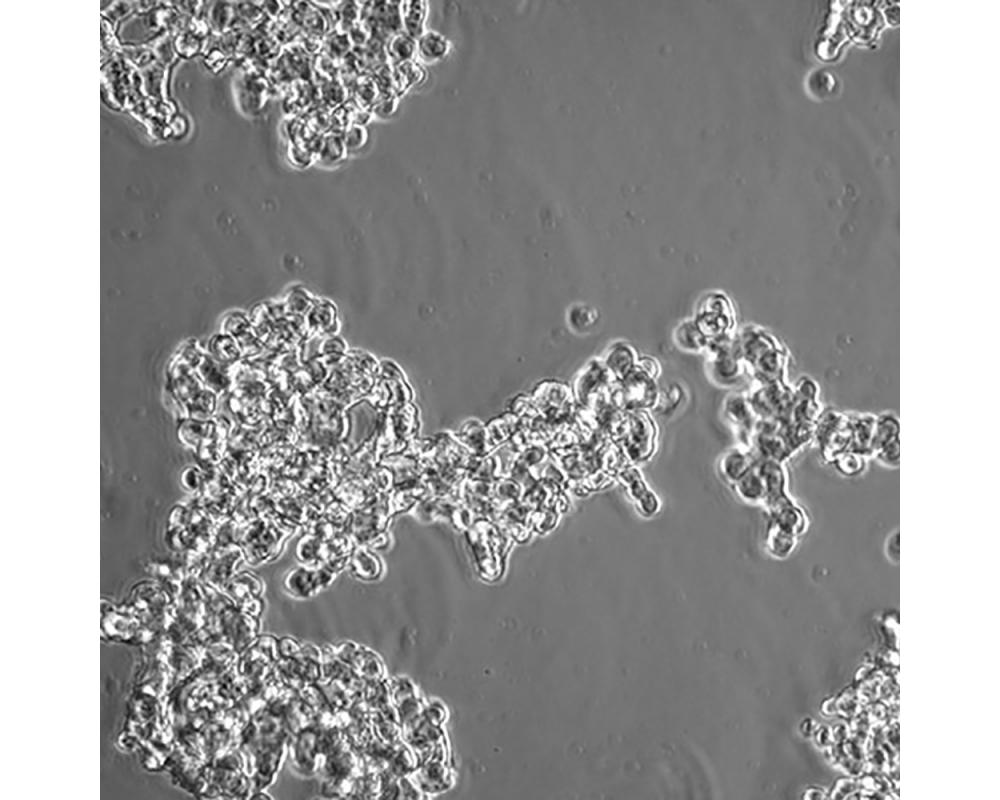

中文名稱 人小細胞肺癌細胞

組織來源 小細胞肺癌;骨髓轉移;男性

生長特性 懸浮

培養基 RPMI-1640+10%FBS+1%P/S

培養條件 Atmosphere: Air, 95%; CO2, 5%。Temperature: 37℃